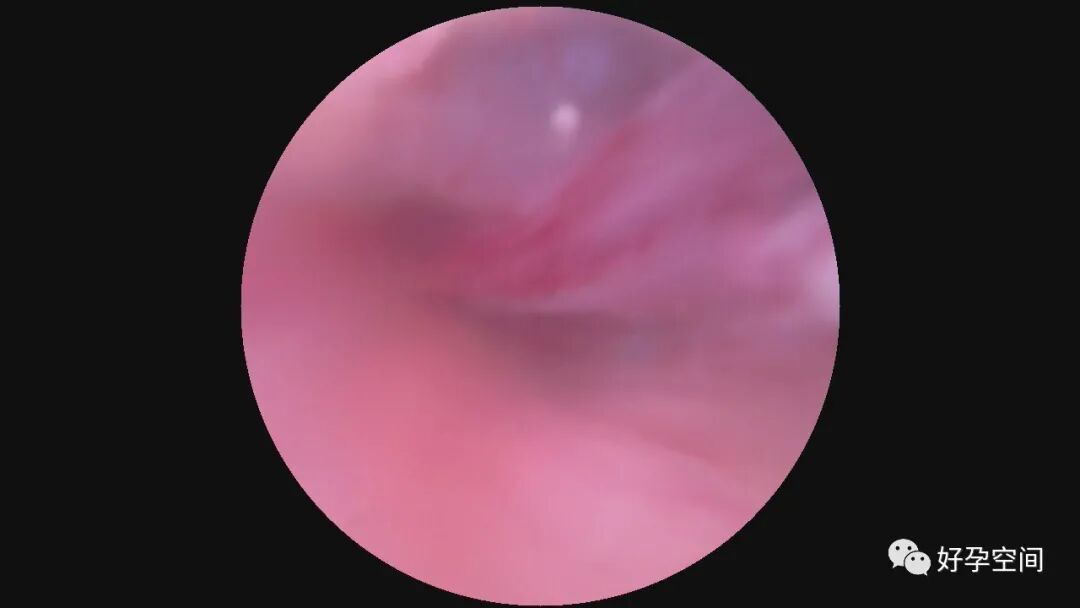

病例4:30岁,G2P1,剖宫产1次。本次停经40+天,计划外妊娠。一次性宫腔镜见胚胎着床于宫腔左后壁,约3cm*3cm*2.5cm,摘除胚胎后宫腔形态正常,双侧输卵管开口可见。